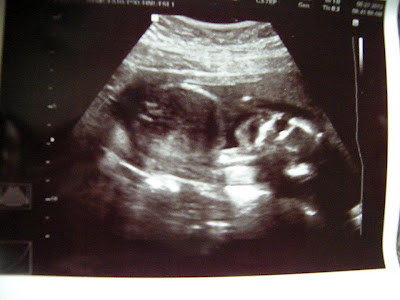

Speaking of mini Allen- this little guy, isn't soo little. I was 19wks on the money when we went in for our ultrasound on Wednesday. "Tate" is measuring 20wks 3 days... that is a whole week and a half more than what I am now, and there is no way we can be off by that much. He is a very lazy baby soo far... he laid still the whole time, keeping his feet crossed, and crossed his arms over his face- putting his hands over his eyes. He lays sideways across my belly- smart guy! There is more room that way too. The placenta is just behind my belly button, so even if this little guy wanted to get feisty, he would have to kick my sides or my back- just like he did the other day. I got a nice kick into my lower back a couple of times. But for the most part this guy is pretty mellow, and so am I- this freaks Allen out that I'm not so wound up anymore. I laugh and tell Allen, since he is such a mellow guy, this baby must take after him quite a bit, because "Tate" has also mellowed me out- from the get go.

So far, I am still at -4lbs 14oz... I gained 3.2lbs back since my last appointment. My blood pressure is staying nice and low- probably why I get dizzy spells at least once a day. The nurse that took us to the room was extra bubbly- I want to know what she is on, to be that bouncy at 8am. She took my blood pressure, and weight, then took us to the room, got me situated on the table, got the DVD set up ready to go, and gave me one of those pad protector things you usually sit on, on the doctor's table, and stuffed it down over my shorts, after I rolled them down, to "Keep the gooo off you're panties"... I told you she was something else. Hayleigh had fun pushing the stool around the room, until the doctor came in, then, it was down to business. Hayleigh ended up watching for the first few minutes, then was running around the room, and then trying to get on the table with me. The doctor was waving the wand all over my belly, found baby "Tate's" head immediately, measured it, then was scanning all around. I thought I saw a weenie for a second- (I did find it again, watching the ultrasound DVD over again). Anyway, he slipped, and started calling the baby, "He"... that then just confirmed what I thought I had seen. Anyway, after the usual measurements, and listened to our little boy's heartbeat. Still makes me cry hearing it. It was 137 bpm... I really knew we were looking at a boy then too- Hayleigh's stayed up in the 150's until I went in to have her- 2 years ago from today :) Allen even made a comment about it. Then, the doctor looked at the spinal cord, and umbilical cord, everything looked just perfect. I learned something new, the twistier the umbilical cord, the better the cord- and his was twisty!! I guess they have less problems with fetal distress, cords wrapping around the baby, or kinking... He then started toward the bottom, but, "Tate" had his feet crossed, and was not wanting to show everything off. I just thought to myself- go figure... Anyway, we finally got to see a weenie, and got a picture of it- you can clearly see it watching the ultrasound- "Tate" just did not want to give us a show I guess. I was excited to say the least. I never dreamed that we would have a boy and a girl- one of each. Perfect! I purposly did not go through any of Hayleigh's baby clothes before the appointment, and bought girl stuff, just to see what we would get. I knew if I started getting Hayleigh's old baby stuff organized, we would have another girl for sure! It really did not matter to me- just a healthy baby, but, I really wanted Allen to get to have a little boy too. So, after scheduling our next appointment, we left, calling, texting, and posting facebook all at once. I loved hearing Allen's Grandparents squeal- they had a bet for $100 Allen's grandma said girl, his grandpa, said boy. Allen's mom was the funniest- she screamed and cried. I had her on speaker phone, on my phone, while Allen had his grandparents on his phone on speaker, so they could all hear each other's reactions. I think Allen's mom was the most emotional- it was soo sweet. Everyone else was really excited and happy- I sat there trying to take it all in, and enjoy the moment, but in the back of my mind, even though I was excited and happy that the baby was healthy, and a boy, I knew this would be the last time we would be making this phone call to everyone. I guess it is just the fact that it took soo long to get Hayleigh, I don't want to be done having these moments, but I want to be done having kids after "Tate". Two is plenty, and we will be happy with two, but the thought of being done having kids, makes me feel old. Allen still has not done a happy dance that I have seen. This baby was all him... I told him that. No doctors, or medical intervention this time.. what ever we got was all us, or him.. I'm just completely surprised that everything has worked out like it has- who would have ever guessed, we would have 2 kids by the time- actually before we both turned 30 years old, we would have one girl, and one boy, they would both be healthy, and we would be happy. I'm still in disbelief that this is really my life, and this is really all happening right now. I don't think that I could be any happier than I am right now. I feel great, look pregnant, and we are all happy, and healthy, and doing well.

As you know, I have mentioned before, Allen will be naming this baby- so he now has two names he likes picked out.. Tate- because I've craved taters, or potatoes, and Reid, or Reed. Reid/Reed popped up in the waiting room at the doctor's office just before we went back. I found it in a magazine, and mentioned it to Allen- who loves Storm Chasers on Discovery Channel- but the name Reid/Reed is different than any name in our families. Having a boy this time is nice in the sense that both of our kids will have our middle names- Hayleigh has mine, and "Tate" will have Allen's, which is Allen. Just worked out wonderful if you ask me! Anyway, this post is long enough, so I will end with a few of the pictures from the ultrasound... We are beyond blessed!!!!

| looking at "Tate" from the front- has hands on face, trying to cover eyes- like Hayleigh did when I was carrying her |